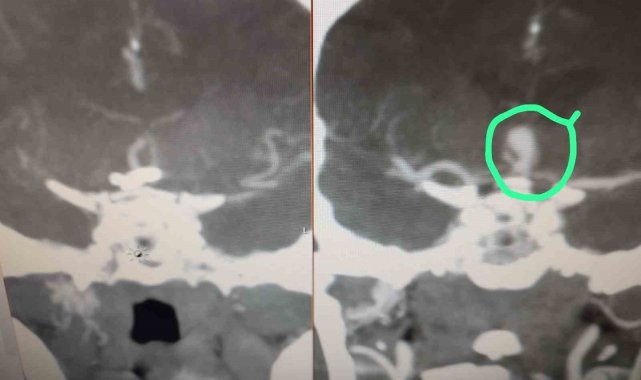

Antalya'nın Serik ilçesinde beyninde baloncuk (anevrizma) tespit edilen hasta, Serik Devlet Hastanesi'nde kaş üzerinden minimal bir kesi ile gerçekleştirilen operasyonla sağlığına kavuştu.Beyninde anevrizma tespit edilen hasta, Serik Devlet Hastanesi'nde kaş üzerinden minimal bir kesi ile gerçekleştirilen operasyonla sağlığına kavuştu. Beyin ve sinir cerrahisi uzmanları Op. Dr. Ömer Elçik ve Op. Dr. Salim Tekir tarafından uygulanan yeni yöntem sayesinde hastanın ameliyat sonrası sürecinin hem daha konforlu geçtiği hem de estetik açıdan iz bırakmadığı bildirildi. Geleneksel beyin cerrahisinde kullanılan geniş kesiler yerine uygulanan modern teknik, özellikle yüz bölgesinde iz kalmasını istemeyen hastalar için önemli bir gelişme olarak değerlendiriliyor. Operasyonun ardından hasta kısa sürede taburcu edildi.Serik Devlet Hastanesi Başhekimi Serkan Kurt, bu tür yenilikçi cerrahi tekniklerin hem iyileşme sürecini hızlandırdığını hem de hasta psikolojisine olumlu katkı sağladığını söyledi.

Anevrizma ameliyatında estetik ve konfor

Antalya'nın Serik ilçesinde beyninde baloncuk (anevrizma) tespit edilen hasta, Serik Devlet Hastanesi'nde kaş üzerinden minimal bir kesi ile gerçekleştirilen operasyonla sağlığına kavuştu.